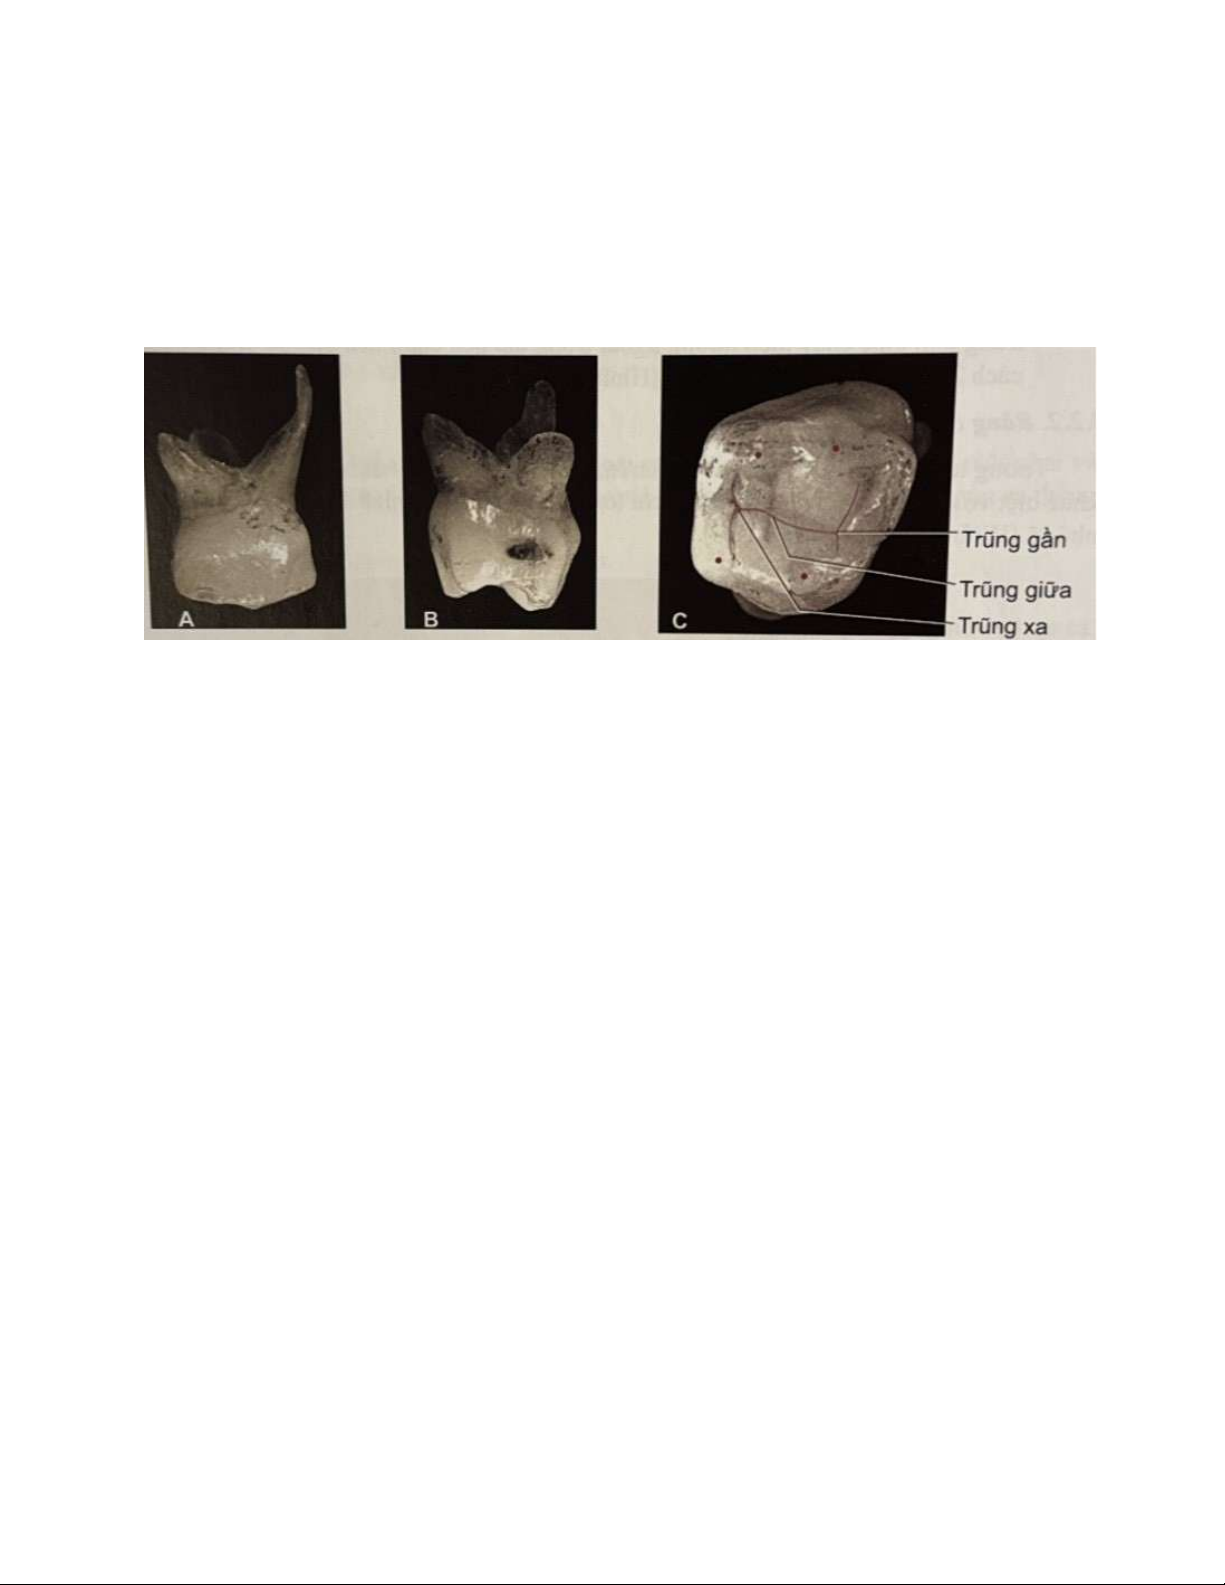

Răng có ba trũng theo thứ tự nhỏ dần từ trũng tam giác gần, trũng giữa và trũng xa.

Đáy các trũng đều có hố (Hình 12l). Rãnh mặt nhai dạng chữ H (Hình 8.15C),

trong đó rãnh giữa nối trũng tam giác gần và xa. Rãnh trong trũng tam giác chạy lOMoAR cPSD| 59561451

theo hướng ngoài trong tạo nên cạnh bên chữ H. Rãnh phân cách 2 múi gần không đặc trưng (Hình 12i).